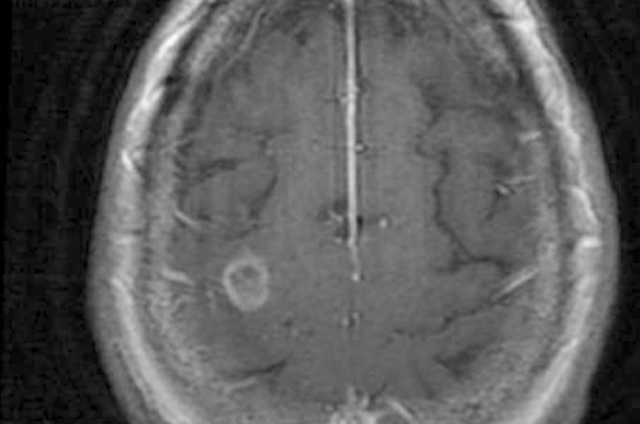

Los médicos le prescribieron medicamentos, sin embargo nada disminuyó el sarpullido; poco después la mujer padeció de un accidente cerebrovascular y tras los análisis, la tomografía computarizada mostró una lesión de media pulgada en su cerebro.

La mujer entró al quirófano para que se le extrajera el área dañada, sin embargo la paciente desarrolló parálisis en un brazo y en una pierna, poco después la biopsia reveló que padecía una infección por amebas en el cerebro.